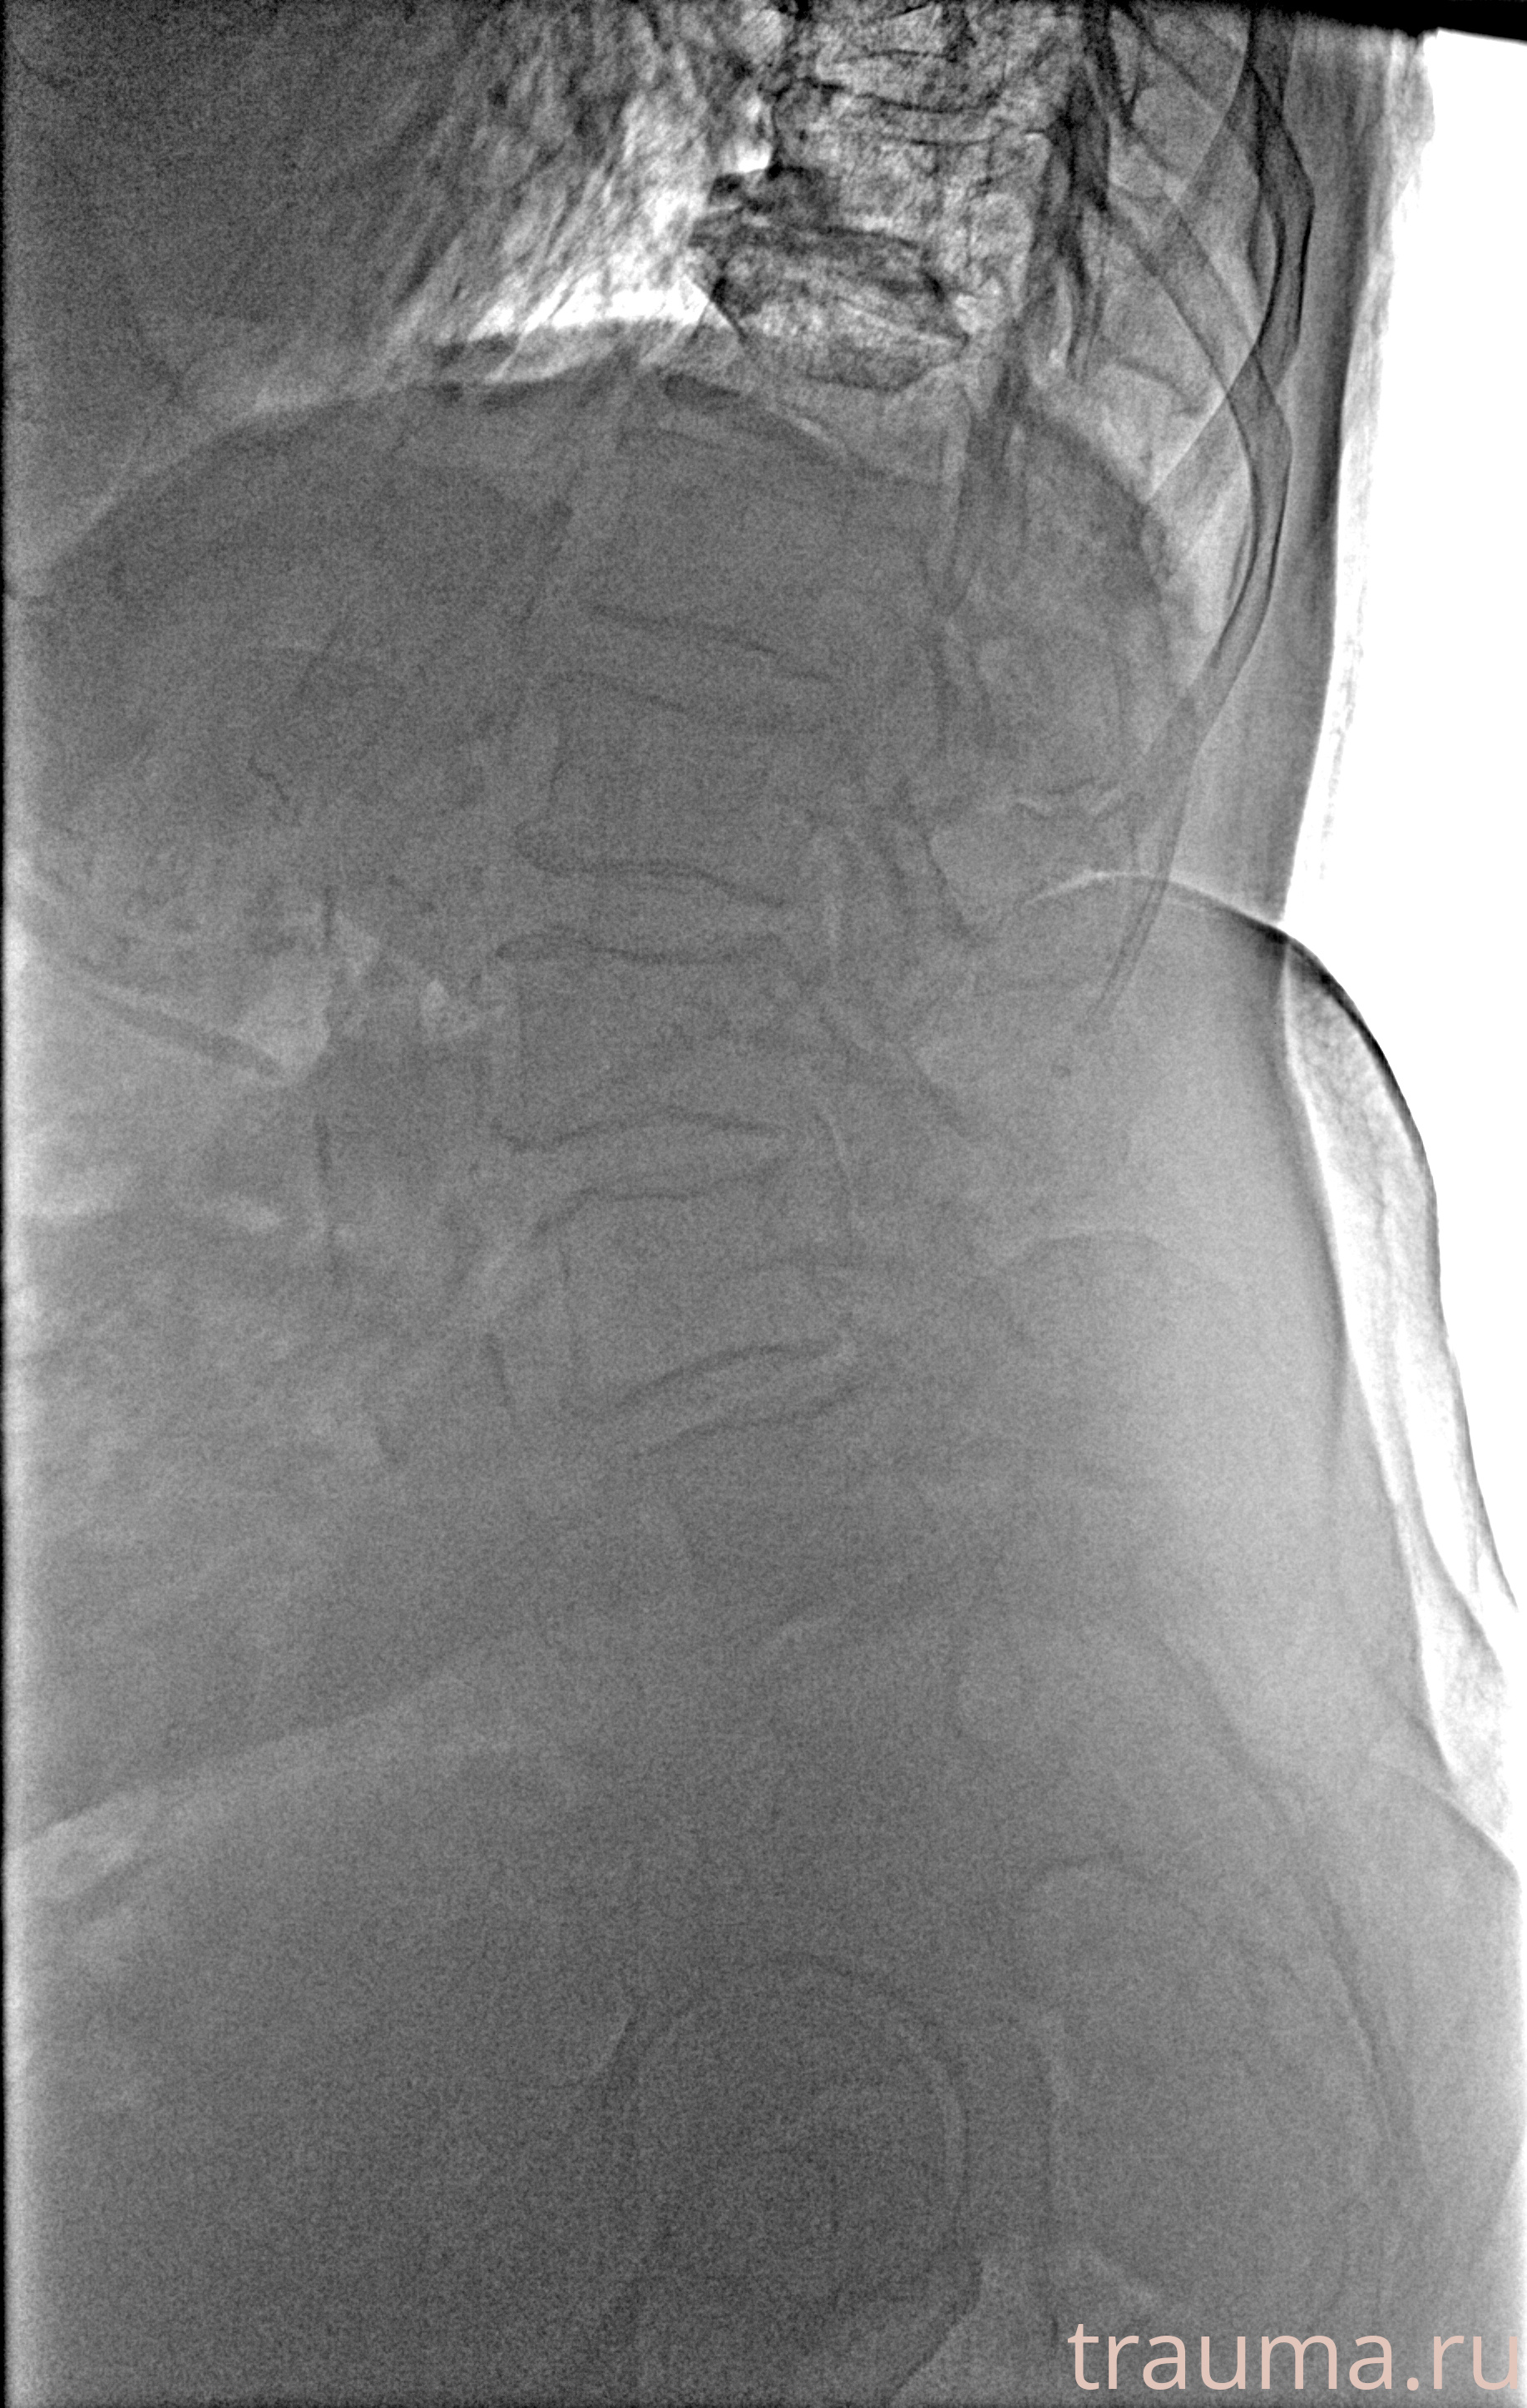

Рентгенограммы

Рентген на дому: по вашему адресу приезжает врач-рентгенолог, травматолог-ортопед с мобильным рентгеновским аппаратом, проводит диагностику травмы или заболевания, делает необходимые рентгенограммы, дает рекомендации по дальнейшему лечению. Получить качественные снимки в домашних условиях возможно благодаря уникальной методике, разработанной МосРентген Центром для института  Склифосовского